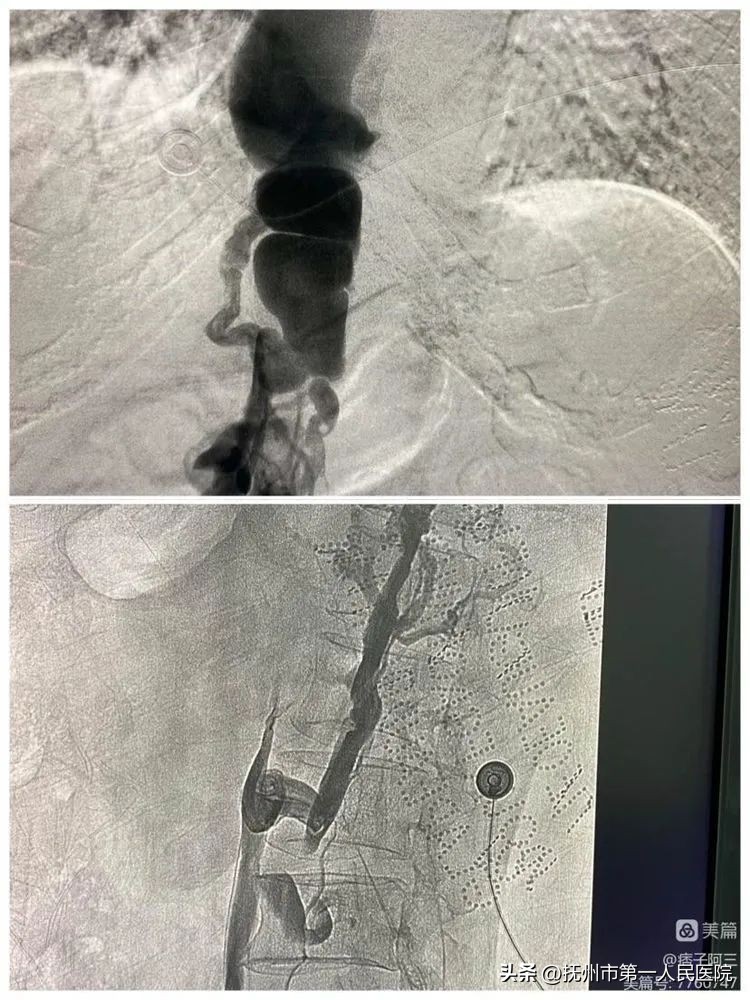

下腔静脉开通后给予下腔静脉球囊(F8—F14)逐渐扩张成型

下腔静脉球囊(F8—F14)逐渐扩张成型结束后立马造影、发现下腔静脉通畅

10分钟后再次造影发现、下腔静脉回缩再次狭窄、患者下腔静脉长段闭塞狭窄遂行下腔静脉支架植入